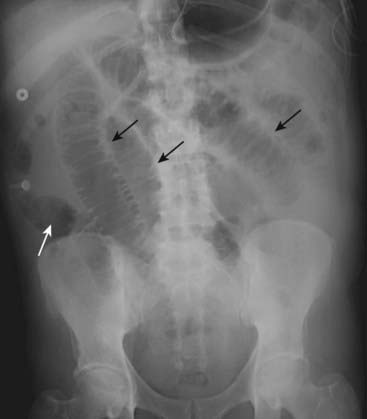

image

Figure 14-4 Step-ladder appearance of obstructed small bowel.

As they begin to dilate, small bowel loops stack up, forming a step-ladder appearance usually beginning in the left upper quadrant and proceeding, depending on how distal the small bowel obstruction is, to the right lower quadrant (solid black arrows). The more proximal the small bowel obstruction (e.g., proximal jejunum), the fewer the dilated loops there will be; the more distal the obstruction (e.g., at the ileocecal valve), the greater the number of dilated small bowel loops. This was a distal small bowel obstruction caused by a carcinoma of the colon which obstructed the ileocecal valve.